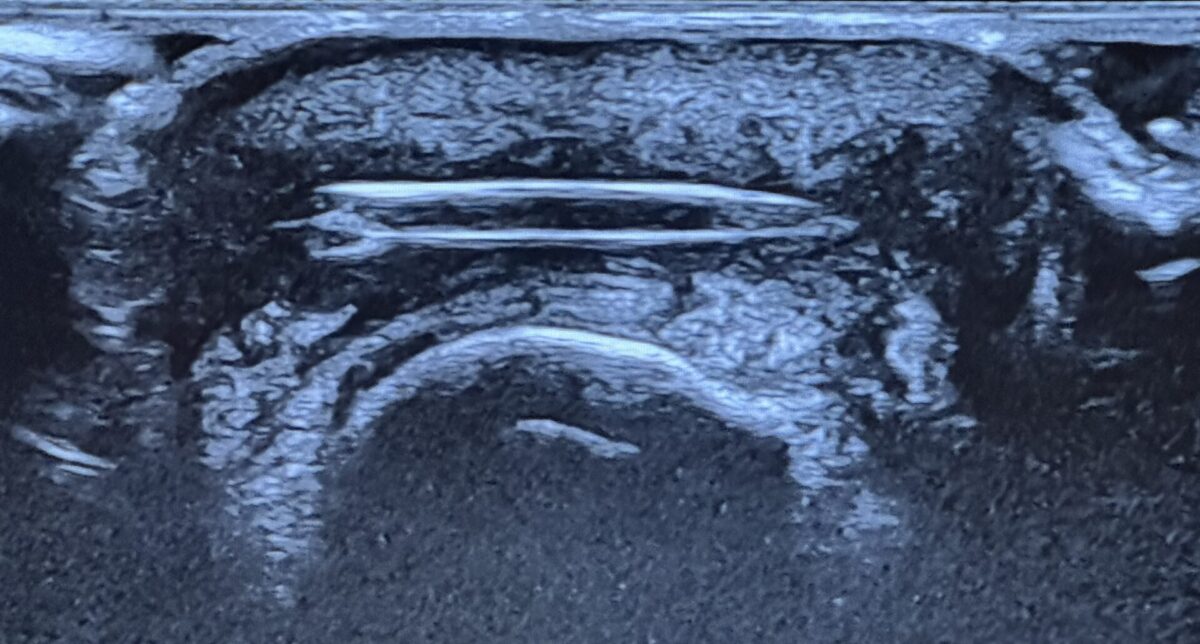

First an ultrasound. As you can see from the below picture, yes… there was a spine in my finger (to the delight of the radiologist!). The GP was not interested. A hand specialist was needed.